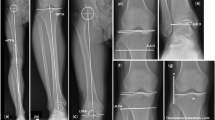

Radiological parameters

Radiological parameters were assessed on an anteroposterior long-axis radiograph under single-limb standing X-ray and standing lateral radiography preoperatively, one month, 1 year and 2 years postoperatively by two orthopaedic surgeons (Y.K. and M.K.). The intra- and interobserver reliabilities of each measurement were assessed by determining the intraclass correlation coefficient (ICC). Radiological parameters included the hip abduction angle (HAA), hip-knee-ankle angle (HKA), lateral distal femoral angle (LDFA), medial proximal tibial angle (MPTA), weight-bearing line ratio (WBLR), joint line convergence angle (JLCA), knee joint line obliquity (KJLO), joint space width (JSW), posterior tibia slope (PTS), Caton-Deschamps index (CDI), lateral distal tibial angle (LDTA), and ankle joint line obliquity (AJLO). The HAA was defined as the angle between the femoral mechanical axis and vertical axis to the ground with abduction. (Adduction: positive) (Fig. 4A) The HKA was defined as the angle between the mechanical femoral axis and the mechanical tibial axis. (Valgus: positive) (Fig. 4B) The LDFA was defined as the lateral angle between the femoral mechanical axis and the femoral distal joint line. (Fig. 4C) The MPTA was defined as the medial angle between the proximal tibial joint line and the mechanical tibial axis (Fig. 4C). The WBLR was defined as the ratio (%) of horizontal distance to WBL from the medial edge of the tibial plateau, as d/w × 100. (Fig. 4D) The JLCA was defined as the angle between the joint line of the distal femur and the joint line of the proximal tibia. (Lateral opening: positive) (Fig. 4E) The KJLO was defined as the angle between the joint line of the proximal tibia and a parallel line to the ground. (Lateral inclination: positive) (Fig. 4F) The JSW was defined as the distance (mm) between the apex of the medial femoral condyle and medial tibial plateau (Fig. 4 G). The PTS was defined as the angle between a parallel line to the ground and the posterior inclination of the tibial plateau (Fig. 4H). The CDI was defined as the ratio (%) of the distance to the lowest point of the articular cartilage on the patella from the tibial articular edge, as a/b (Fig. 4H). The LDTA was defined as the lateral angle between the joint line of the talus and the tibial mechanical axis (Fig. 4I). The AJLO was defined as the angle between the joint line of the talus and a line parallel to the ground. (Lateral inclination: positive) (Fig. 4J).

Radiological parameters. (A) hip abduction ankle (HAA), (B) hip knee ankle (HKA), (C) femorotibial angle (FTA), (D) lateral distal femoral angle (LDFA) and medial proximal tibial angle (MPTA), (E) weight-bearing line ratio (WBLR), (F) joint line convergence angle (JLCA), (G) knee joint line obliquity (KJLO), (H) joint space width (JSW), (I) posterior tibia slope (PTS) and Caton-Deschamps index (CDI), (J) lateral distal tibial angle (LDTA), (K) ankle joint line obliquity (AJLO).